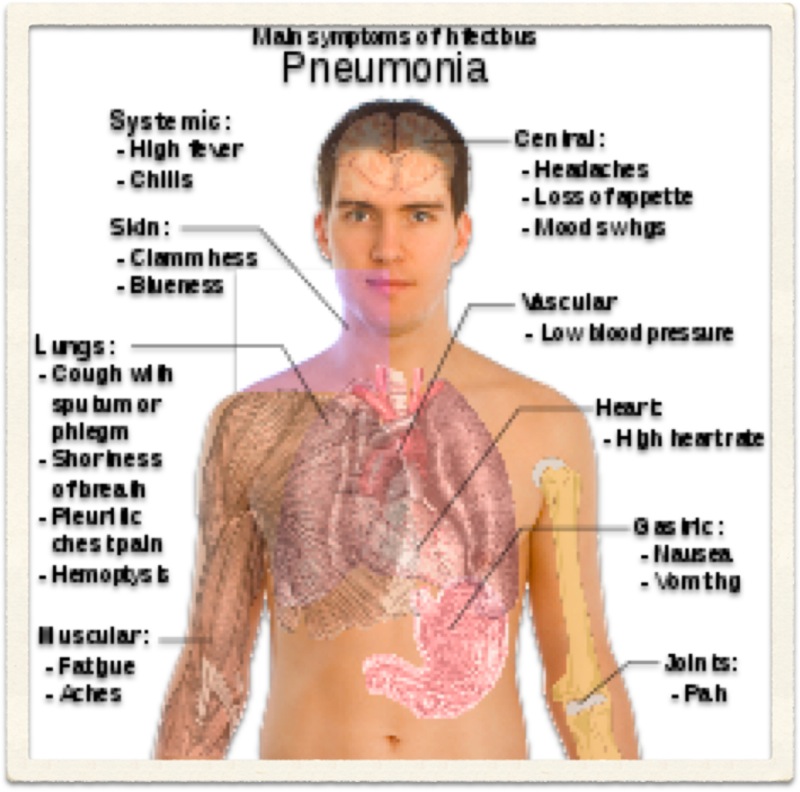

Chronic Obstructive Pulmonary Disease (COPD) is an 'umbrella' term for people with chronic bronchitis, emphysema, or both. With COPD the airflow to the lungs is restricted (obstructed). COPD is usually caused by smoking. Symptoms include cough and breathlessness.